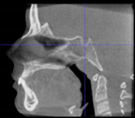

Three points determined the Acta plane: O, F right (FR), and F left (FL) (Table 2). Point O is the midpoint between the most craniodorsal point of the dorsum Sella and the most posterior dorsal point of the Basion in the midsagittal plane (Figure 1). Both points F are a result of the intersection between two lines: the line that connects the most inferior points of the lower orbital margins, right and left, and a line perpendicular to this line that runs through the most external points of the orbital margins, right and left (Figure 2). The new transverse reference plane, the Acta plane (Figure 2), is created by connecting the O-point (Figure 1) with FR and FL (Figure 2).

Figure 1.

Point O (green dot) is the midpoint between the dorsum Sella (Se) (red dot) and the Basion point (Ba) (yellow dot).